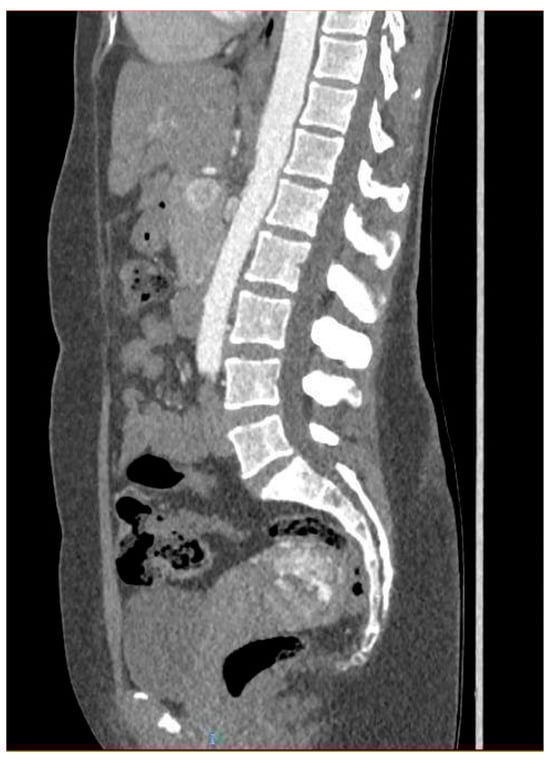

Ultrasonography showed an endometrial cavity occupied by a protruding formation in the uterine cavity measuring 38 × 15 mm, compatible with a uterine AVM (Figure 1). The presence of vascularisation of the right lateral uterine wall was noted, and pulsed Doppler showed a peak systolic velocity > 100 cm/s (Figure 2).

Figure 1. Transvaginal ultrasound with suspected uterine arteriovenous malformation.